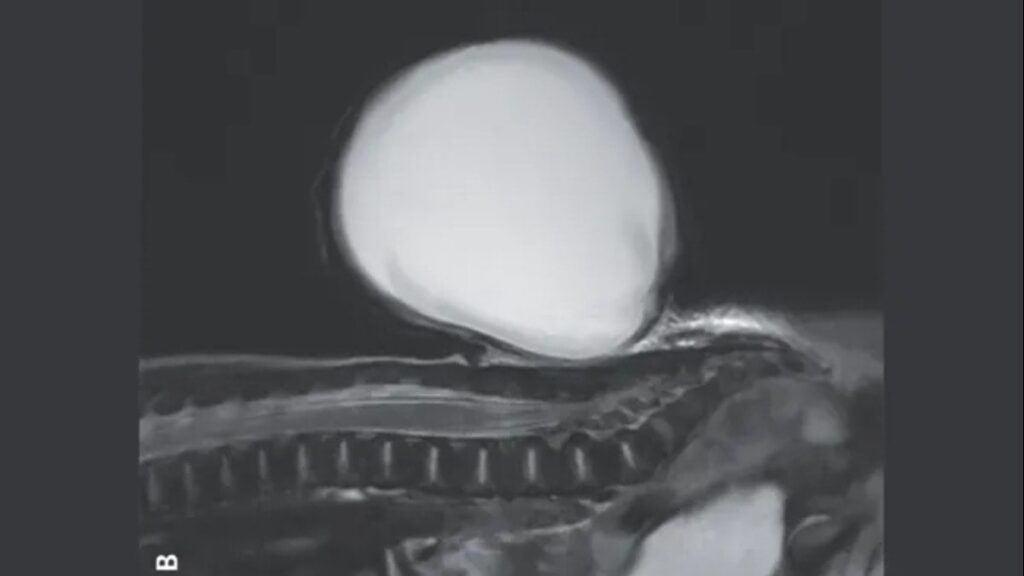

Doktorların kaydettiği görüntüde, bebeğin sırtındaki yapı yaklaşık 7,7 santimetre uzunluğunda, 7,1 santimetre genişliğinde ve 5,3 santimetre derinliğindeydi. Bu yapı, omuriliği çevreleyen dokunun omurgadaki boşluktan dışarı taşmasıyla oluşmuştu.

Spina bifida, bebeklerde en sık görülen doğumsal anomalilerden biridir ve her 10 bin doğumdan 5 ila 8’ini etkiler. Normalde, gebeliğin üçüncü ve dördüncü haftalarında oluşan nöral tüp, beyin ve omuriliği oluşturur. Ancak bu süreçte oluşan bir aksaklık, omurga üzerinde bir boşluğa neden olabilir. Bebeğin durumunda ise meningosel adı verilen spina bifida türü tespit edildi. Bu durum, omuriliği çevreleyen sıvı ve dokunun dışarı taşmasına neden olur.